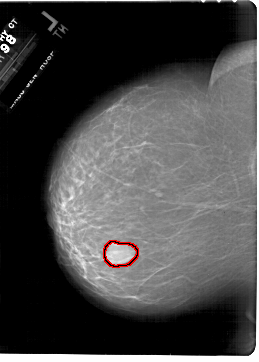

A_1801_1.LEFT_CC

LEFT_CC LINES 6871 PIXELS_PER_LINE 4906 BITS_PER_PIXEL 12 RESOLUTION 43.5 OVERLAY

FILE: A_1801_1.LEFT_CC.OVERLAY

TOTAL_ABNORMALITIES 1

ABNORMALITY 1

LESION_TYPE MASS SHAPE LOBULATED MARGINS CIRCUMSCRIBED

ASSESSMENT 4

SUBTLETY 5

PATHOLOGY BENIGN

TOTAL_OUTLINES 1

BOUNDARY